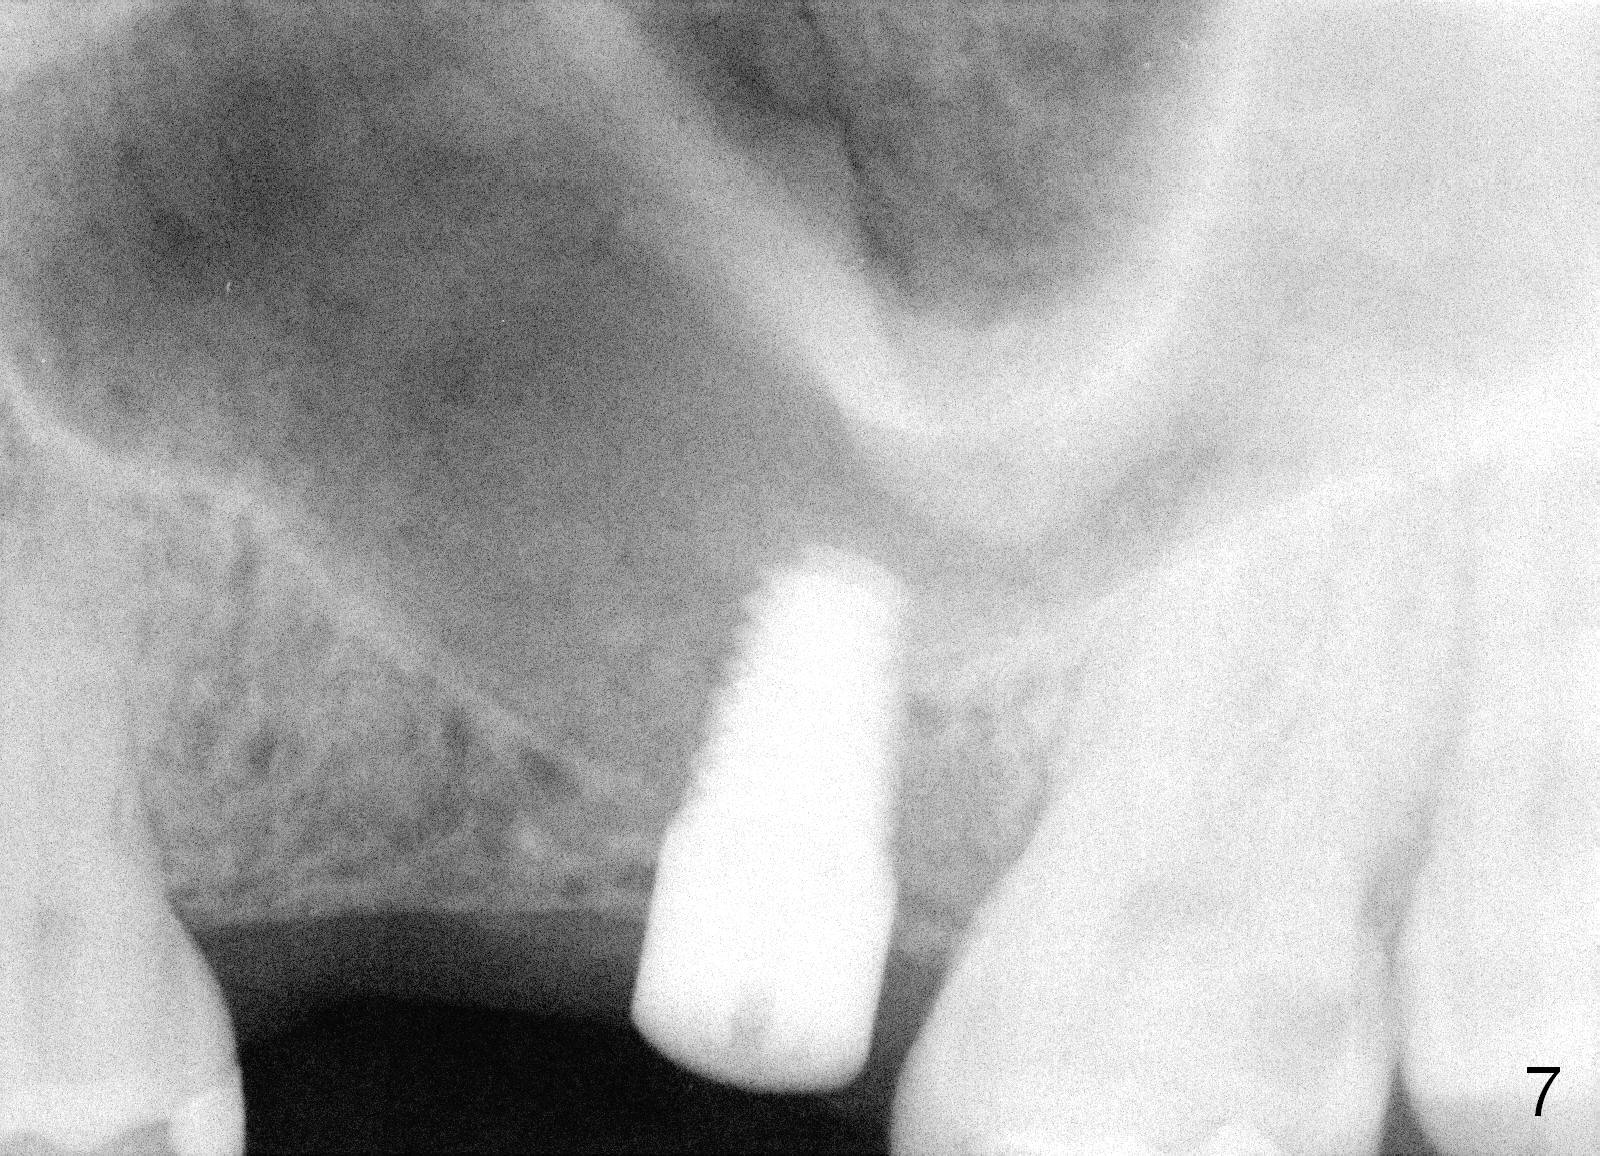

The patient returns for #13,14 implant placement. The ridge appears to be wide buccolingually (Fig.1 mirror view). A 4 mm tissue punch is used for access at the sites of #13 and 14. Osteotomy is initiated by using 3 mm trephine bur at the depth of 4 mm at both sites; 2 mm pilot drill is used to continue osteotomy at 8 mm deep at the site of #13. Sinus lift is accomplished by using tapered osteotomes 2,3 mm 6 mm deep, followed by 4.5x11 mm tap (Fig.2 T); 2 mm pilot drill (P) is reinserted into #13 osteotomy site with inadvertently penetrating the sinus floor. When the tap is removed from the site of #14, the sinus membrane is also found to be perforated. The sinus membrane at both sites is repaired by insertion of collagen dressing before bone graft. A 4x11 mm one-piece implant is placed at the site of #13 slowly hoping that it does not re-perforate the sinus membrane (Fig.3 O). Due to limited restorative height, the abutment portion of the one-piece is expected to be trimmed (Fig.4 O). In case of implant complication or failure, the implant may be difficult to be removed. Therefore the implant at the site of #14 is two piece one (Fig.4,5 I/A, 5x11 and 4x3 mm, respectively). The insertion torques for #13 and 14 are 35/40 and >60 Ncm. Immediate provisionals are canceled mainly because of patient's inability to open wide for long. Perio dressing is placed instead after adjustment of the height of the abutments. The patient experiences one episode of light nasal hemorrhage a few hours postop. Although the patient takes Amoxicillin for 1 week periop, the implant at the site of #13 dislodges 1 months postop (Fig.5). Immediate re-placement with a larger 2 piece one is canceled because of mild infection mesiobuccal to the implant at the site of #14 (Fig.6 >). Exploration around the latter implant reveals possible thread exposure in a small area. After copious irrigation with normal saline, Arestin is placed. Two months post exfoliation, the site is re-entered (Fig.7,8). There is a lingual defect. Osteotomy is initiated as buccal as possible. A 4.5x11 mm tapered tap penetrates the sinus floor without tearing the membrane (Fig.9). The same-sized implant is placed (25/30 Ncm) with sinus lift (Fig.10 *). The lingual defect is bone grafted. There is dehiscence lingually 7 days postop (Fig.11). Impression for final restoration is taken 1.5 months postop because of pending wedding. The crown has been in function for 2.5 months.